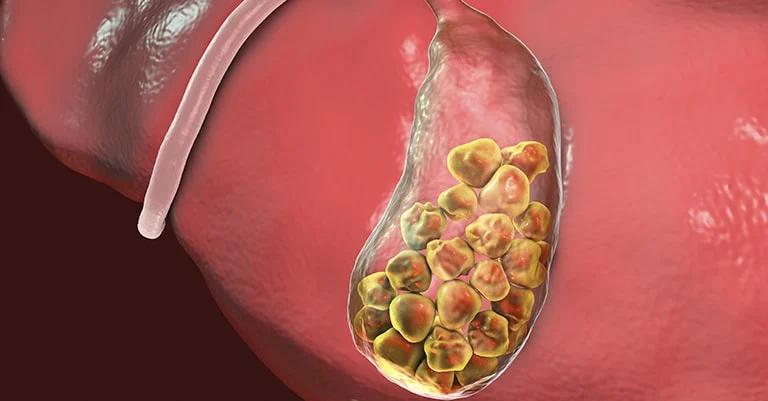

Πρέπει να αφαιρεθεί η χοληδόχος κύστη αν εντοπιστούν πέτρες στη χολή;

Η αναγκαιότητα αφαίρεσης της χοληδόχου κύστης εξαρτάται από τον τύπο των χολόλιθων και τη σοβαρότητα των συμπτωμάτων. Εάν οι πέτρες είναι μικρές και δεν προκαλούν σημαντική ενόχληση, οι γιατροί συστήνουν συνήθως συντηρητική θεραπεία με τακτική παρακολούθηση.

Ωστόσο, εάν οι πέτρες στη χολή προκαλούν σοβαρά συμπτώματα ή επιπλοκές όπως χολοκυστίτιδα, χολαγγειίτιδα ή εάν οι πέτρες είναι πολύ μεγάλες ή πολυάριθμες, οι γιατροί μπορεί να συμβουλεύσουν την αφαίρεση της χοληδόχου κύστης.

Συνοψίζοντας, εάν η αφαίρεση της χοληδόχου κύστης είναι απαραίτητη εξαρτάται από τον τύπο των χολόλιθων, τη σοβαρότητα των συμπτωμάτων και άλλους σχετικούς παράγοντες.